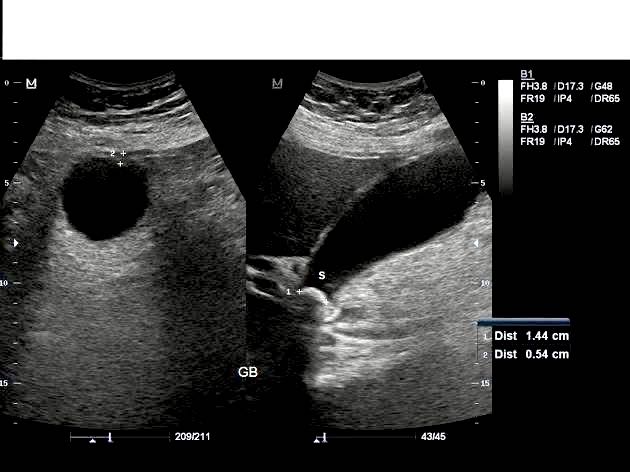

أوَّل فحص يُجرى للتشخيص هو "الإيكوغرافي" الذي يسمح بوضع التشخيص، حيث يُلاحظ وجود : تسمُّك في جدار المرارة > 3 ملم، ووجود سائل حول المرارة، مع وجود ألم عند مرور مسبار الإيكو فوق المرارة "علامة مورفي الشعاعية"، ووجود حصاة مُنحشرة في المِجَلّ أو في القناة المرارية "حصاة غير متحرِّكة بتغيير الوضعيات"، مع زيادة في حجم المرارة لأكثر من 8 سم طولاً و 5 سم عرضاً.

كما يُحدِّد الإيكو سلامة الكبد والقناة الجامعة.